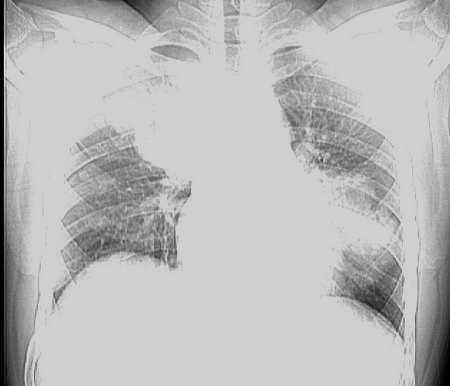

男,18岁。咳嗽,胸闷4天。

肺转移